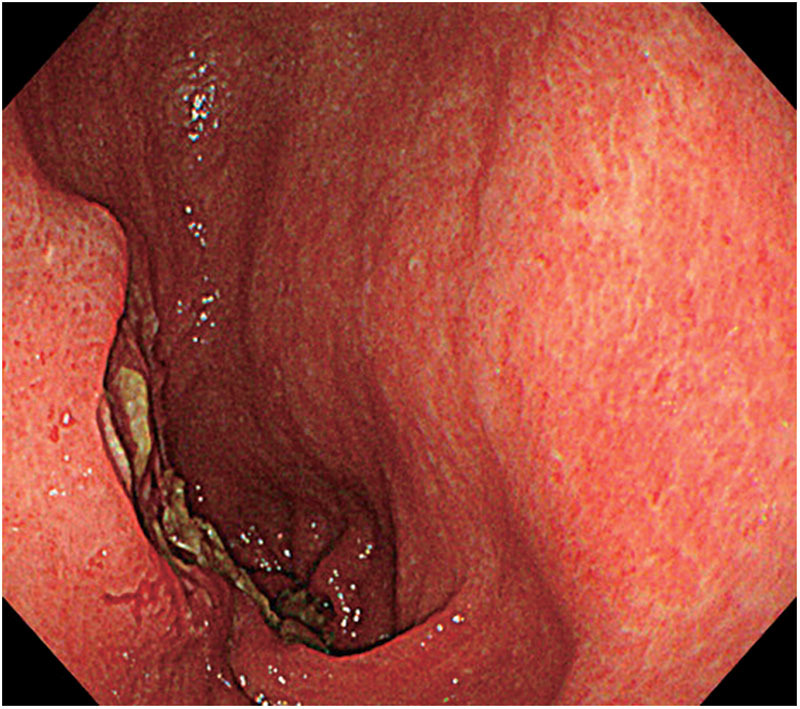

The incidence of gastric tube cancers has increased due to improved survival rates in patients after esophagectomy. However, the optimal surgical approach for gastric tube cancer remains controversial. Here, we report the case of a 70-year-old man with advanced gastric cancer arising from a retrosternally placed gastric conduit, 12 years after thoracic esophagectomy for esophageal cancer. Total resection of the gastric conduit was performed with robotic assistance. Although the working space was limited, secure resection was possible. Continuous en bloc mobilization was achieved with neck dissection, and reconstruction was performed via the same retrosternal route using the ileocolon. The patient was discharged on the 14th postoperative day without any adverse events. Robot-assisted surgery can overcome the technical limitations of laparoscopic mediastinal surgery and has advantages such as improved ergonomics, comfort, and elimination of hand tremors, and therefore may be an option for future minimally invasive surgeries.